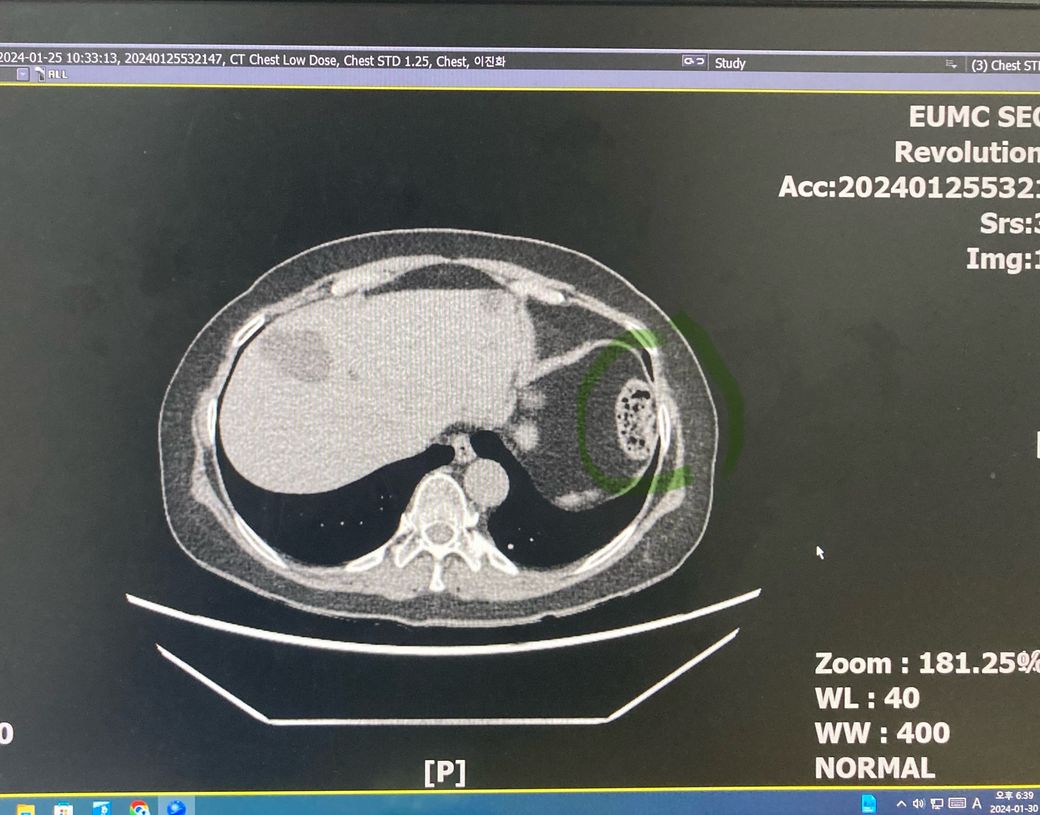

노란색 동그라미 폐 결절을 추적관찰 중인데

위에 사진이 3개월전 아래 사진이 최근에 찍은 사진입니다. 육안으로 봐서는 결절 크기는 변화가 없는것 처럼 보이는데.. 갑자기 초록색 동그라미 부분은 왜 저렇게 변한건가요? 벌집 처럼 생겼는데..... 무슨 문제가 생긴건가요?

저 장기가 뭘 찍은건지도 알려주시면 감사하겠습니다.

폐결절은 말씀하신대로 3개월 전 사진과 비교했을 때 큰 변화가 없어 보여서 추적관찰 하자는 말씀을 들으셨을 것 같습니다.

초록색으로 표시한 부분은 위 안에 있는 음식물로 보입니다.

초록색은 위장의 일부분이니 신경쓰지마세요 정상입니다.

동그라미 표시한 부분은 정상장기이며 대장의 일부분이

잘려 보이는 것으로 생각됩니다

폐결절은 크게 변화가 있어보이지는 않습니다

녹색으로 동그라미 친 부위는 위 속의 음식물이 관찰되는 것일 가능성이 매우 높아 보이는 소견입니다. 크게 걱정할 것 없어 보입니다.